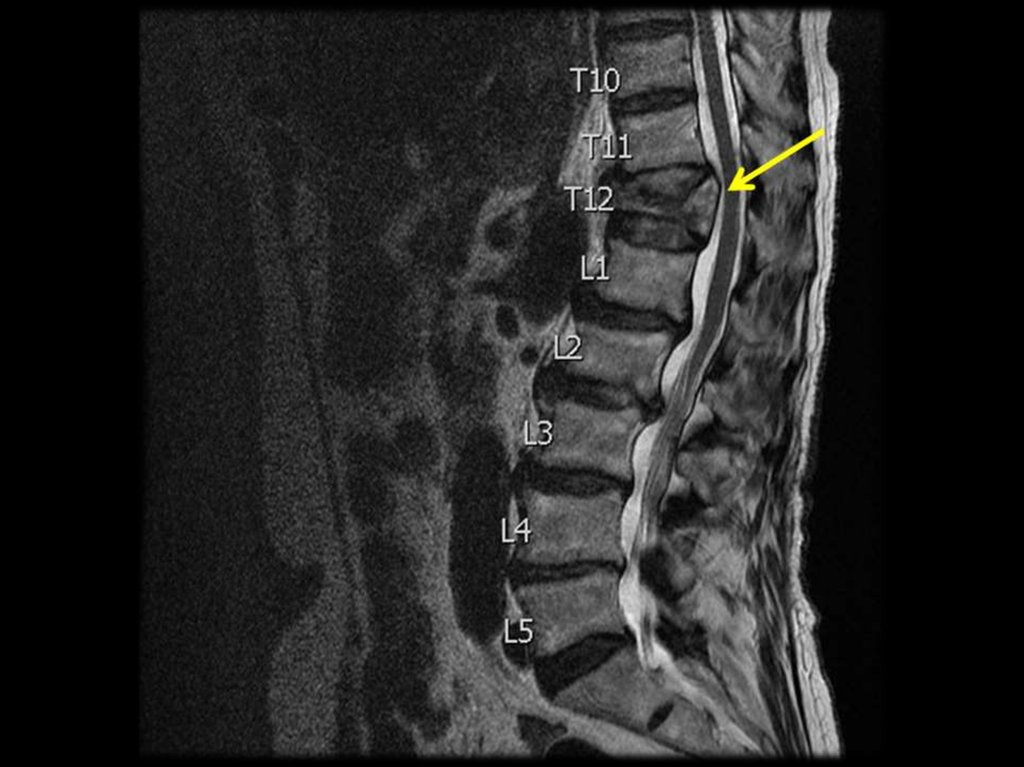

Примеры диагноза:

Тяжёлый стероидный ОП с компрессионным

переломом в грудном отделе позвоночника

(Th 12 – L1), перелом предплечья (в 1998 г).

R-признаки при ОП (R-графия позвонков в

боковой проекции), потеря костной массы

при этом составляет 20 – 30%.

деформация тел позвонков

Виды деформации тел позвонков:

передняя клиновидная;

задняя клиновидная;

двояковогнутая деформация (по типу

“рыбьих”);

компрессионная деформация;

сочетанная.